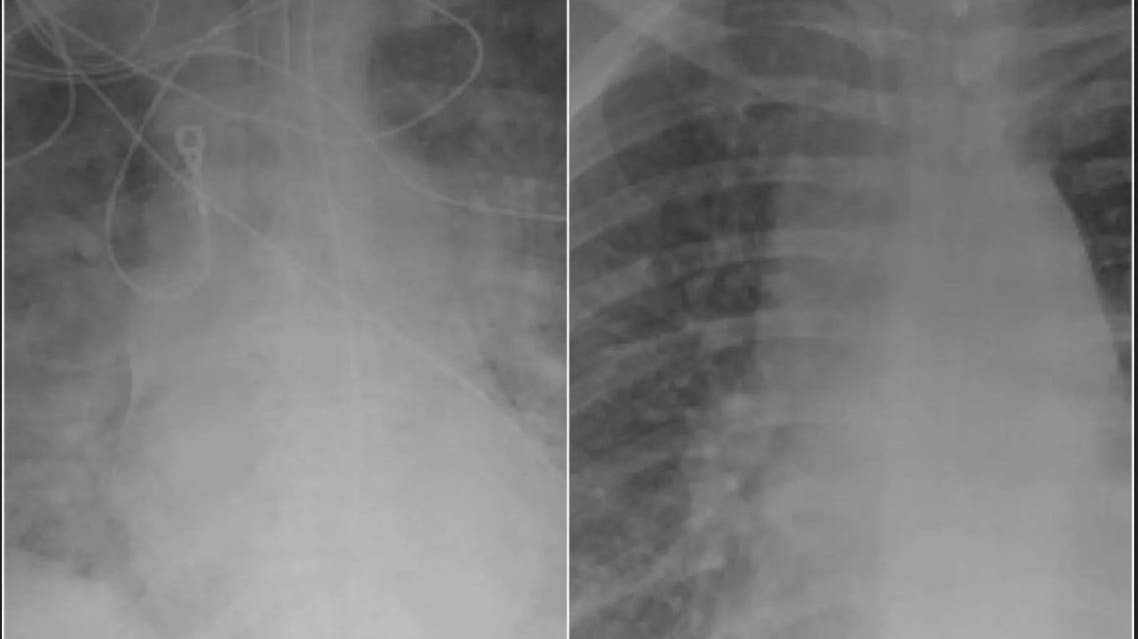

شاهدوا الفرق بين رئتي مصابين بكورونا.. أحدهما تلقى اللقاح والآخر لا